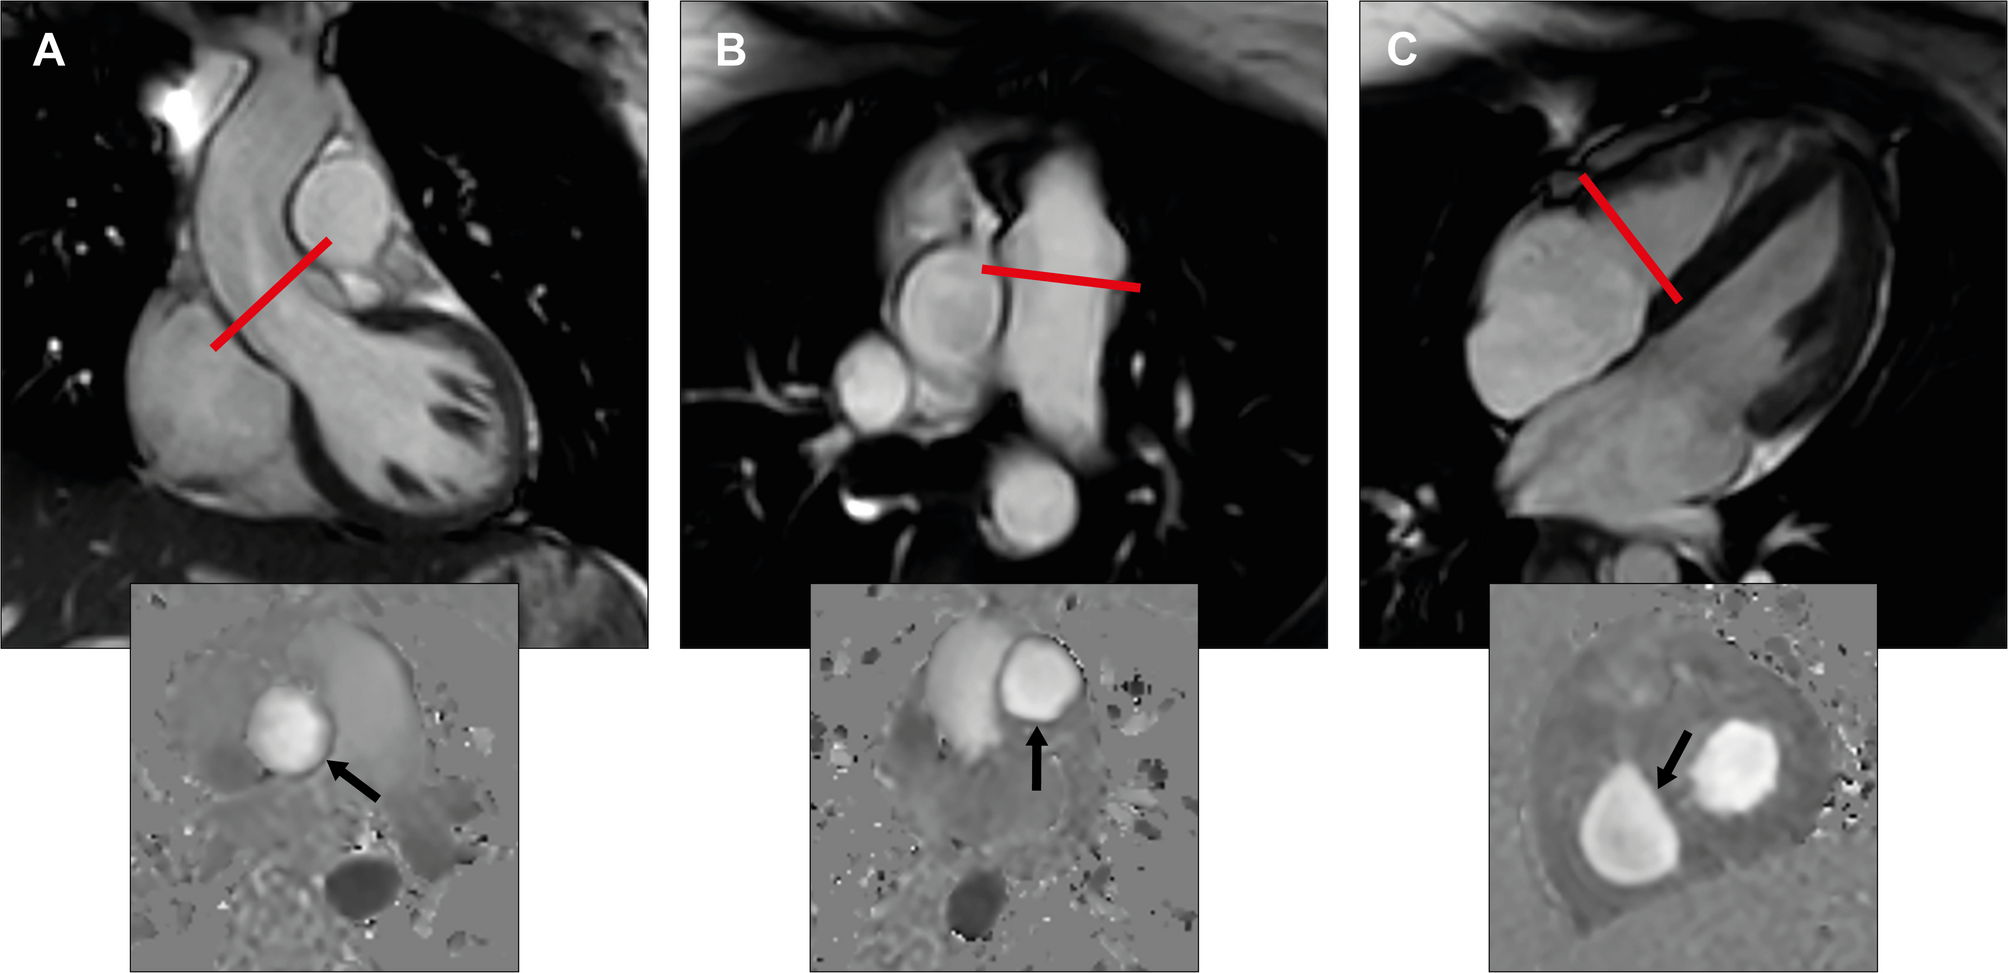

Fig. 1

Image acquisition and analysis for CMR flow volume quantification. (A, B) Left and right ventricular outflow tract view in end-diastole. The red line illustrates the slice position for through plane phase contrast velocity imaging. Quantification of aorta and pulmonary flow is depicted in the corresponding phase contrast image below (arrow). (C) Four -chamber view in early diastole with an open tricuspid valve. The red line illustrates the slice position for through plane phase contrast velocity imaging. The corresponding phase contrast image for tricuspid inflow quantification in diastole is shown below (arrow).